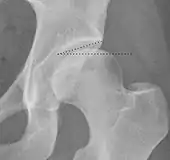

Radiograph of a cam type impingement.

Projectional radiography ("X-ray")is often considered first line for FAI.[10] Anterior-posterior pelvis and a lateral image of the hip in question should be attained.[10] A 45-degree Dunn view is also recommended.[10][19]